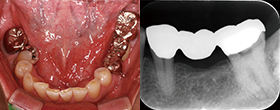

Case2 直線根管

• CC「左下奥違和感」主訴に来院

左下6遠心根に透過像認める

• インレー除去

透過像に一致した部位にサイナストラクト認める

• コンポジットレジンにて隔壁作成

• 作業長確認

最終拡大#30/.04テーパー